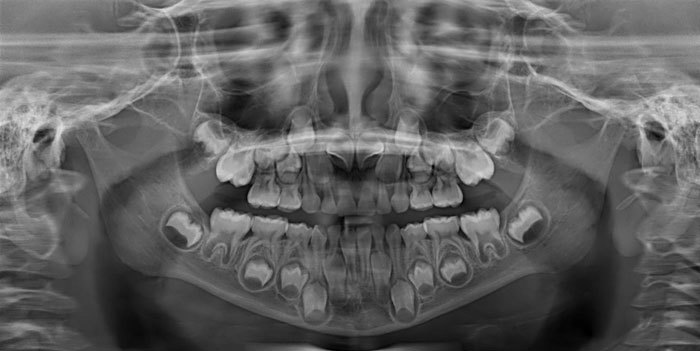

文章插图

儿童口X射线检查对6-12岁之间的孩子仍然令我感到惊奇